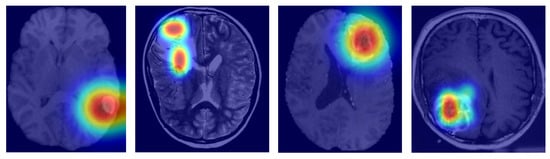

In this study, we also evaluated MGMT-Net’s ability to predict three clinically significant molecular markers: IDH mutation, 1p/19q co-deletion, and TERT promoter mutation, all of which were preoperatively inferred from multi-modal MRI scans. These molecular markers are central to glioma classification under the WHO CNS tumor grading system and play a critical role in patient prognosis, treatment planning, and therapeutic decision-making. The prediction task was formulated as a patient-level binary classification problem, with model outputs compared to ground truth labels obtained from histopathological analysis. On the unified TCGA-GBM/LGG and Erasmus Glioma Database (EGD) test cohort, MGMT-Net achieved AUC scores of 0.94 (IDH), 0.91 (1p/19q), and 0.90 (TERT), outperforming the best baseline model, which reached 0.92, 0.89, and 0.86, respectively. Corresponding classification accuracies were 92.4% for IDH, 88.9% for 1p/19q, and 86.7% for TERT. These results highlight not only MGMT-Net’s strong overall predictive performance but also its enhanced sensitivity to specific molecular markers when compared with leading 3D CNN and DenseNet-based approaches. This performance advantage is primarily attributed to the model’s attention-based global feature pooling strategy, which selectively emphasizes clinically informative regions within the volumetric MRI data during feature extraction Figure 3.

As an example, the model often focuses on the tumor core or ceases to focus on enhancing features when IDH status is being predicted. This focus overlaps with imaging features associated with the mutation. In the table below, these results are presented along with comparisons of MGMT-Net and the best-performing conventional deep learning baseline Table 2.

To gauge interpretability, we came up with Grad-CAM visualizations and attention heatmaps for typical cases stemming from biomarkers. As depicted in Figure 6, MGMT-Net kept on highlighting the tumor regions, which were of utmost biological relevance, during its prediction. In the case of IDH mutation, the most activated areas were around the non-enhancing tumor core; whereas for TERT prediction, the attention was at the enhancing rim and the necrotic boundary; and for 1p/19q co-deletion, the model was focused on the diffuse infiltrative margins seen in the FLAIR sequences.

The noted patterns correspond greatly with the radiogenomic associations that have been mentioned in previous studies and hence, they are an indication of the biological plausibility of MGMT-Net’s predictions. Furthermore, by looking at the CMAF weights, we found modality-specific attribution: FLAIR features were the most prominent in the peritumoral edema delineation, T1ce showed the vascular regions, and T2 was for the boundary sensitivity. Such findings, combined, lead to the conclusion that MGMT-Net is not only a predictor of accurate outcomes but also a provider of the interpretable cues that are consistent with neuro-oncological knowledge.